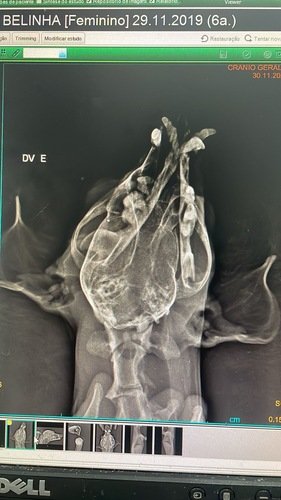

Eu morro de medo de fogos e ontem, por conta do jogo, eu pulei da sacada de casa e estou cheia de machucados - o pior deles é a fratura da mandíbula!!

Estou internada e sendo medicada, porque isso dói muito! Fiz todos os exames e estou me comportando muito bem, mas os tios veterinários falaram que precisarei de cirurgia!